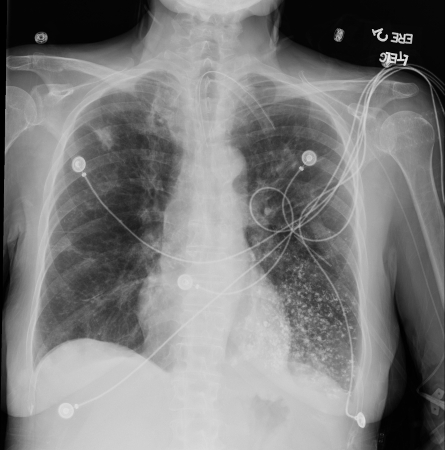

Aspiración de bario. Se produjo una ingesta de bario en una mujer de 53 años. Las imágenes revelaron material hiperdenso centrado en la vía respiratoria en el lóbulo inferior izquierdo compatible con bronquiolitis por aspiración de bario. Se confirmó una fístula traqueoesofágica

De la colección del Dr. Augustine Lee; utilizado con el permiso de la Fundación Mayo para la Educación e Investigación Médica, todos los derechos reservados